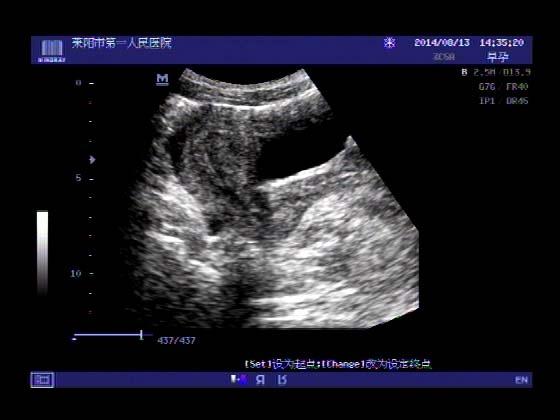

超声入门贴341:宫外孕(阴超的魅力)

女,32岁,停经15天,

一周前在上极医院检查:化验尿HCG阳性,血HCG400多,超声检查问见明显孕囊,让随访。

很典型,图像不错,阴超的优势!!